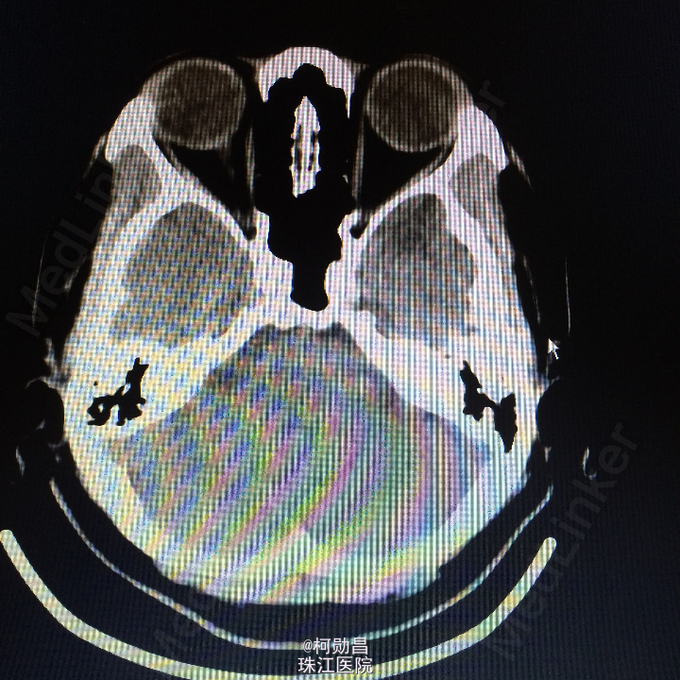

间断性眩晕伴头痛10余年 患者10年来无明显诱因间断性出现起床后眩晕,为天旋地转状,伴头痛、恶心、呕吐,严重时会出现肢体抽搐,双眼紧闭,无口角抽搐、意识障碍等。大约每年发作一次,数小时后自行好转,自服药物治疗(具体不详)。患者1个月前再次出现上述症状,遂至我院诊治:查头颅MR提示:左侧颞极前部皮层及皮层下异常信号影,不排除肿瘤。建议增强扫面。

查体:神经系统查体未见明显异常 头颅CT:左颞极前部占位,建议增强检察 头颅MR:左侧颞极前部皮层及皮层下异常信号影,不排除肿瘤。

诊断:脑膜血管瘤 处理:开颅手术切除,术后病理提示:(左颞极)脑膜血管瘤